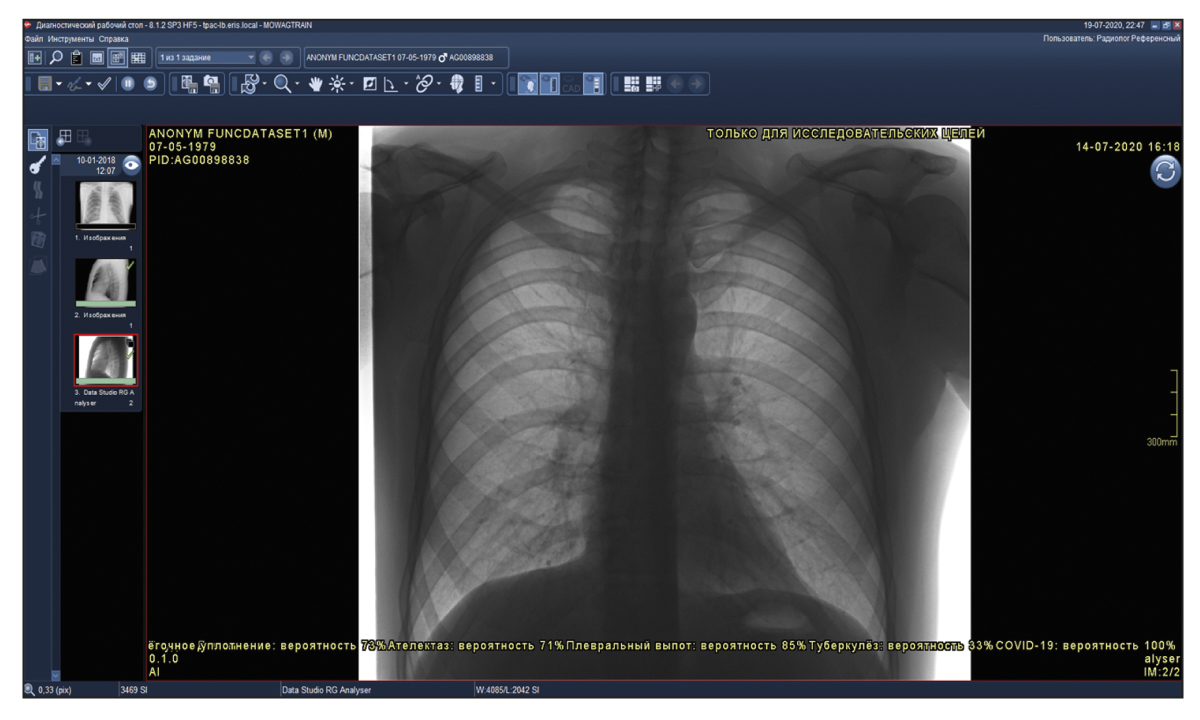

Functional testing is a stage wherein software functions specified by a supplier are checked for availability and functionality. This testing is performed at the technical and clinical levels. On a technical level, the software is assessed based on the following criteria: prioritization of research (triage), availability of an additional series of images from the software, presence of the other series’ name, presence of a graphical designation of software on the images of the different series, presence of a warning label “For research purposes only” on images and in DICOM SR, possibility of series synchronization, displaying the probability of abnormality, indication of the category of abnormality, and availability of complete DICOM SR protocol structure (Figures 2 and 3).

Fig. 2. Main components of the result of using artificial intelligence–based software with images: A reference example.